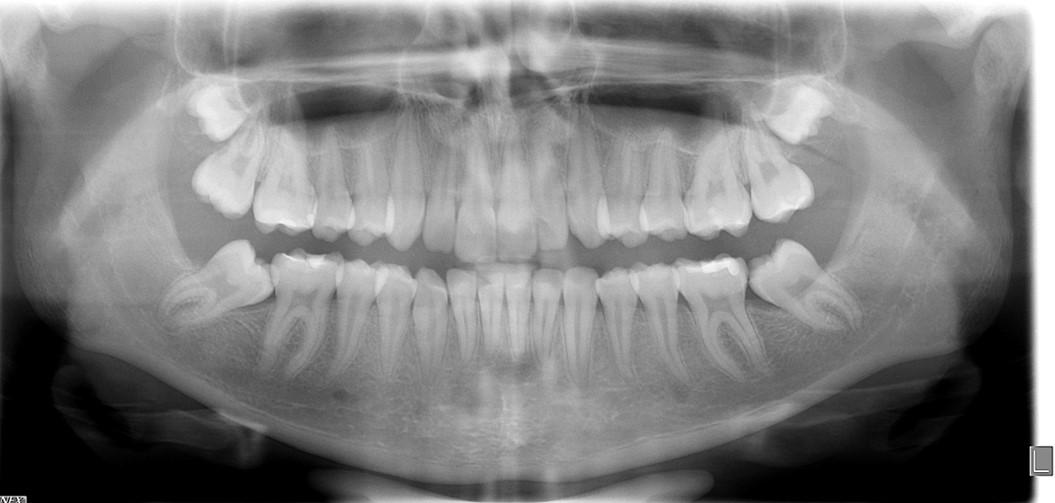

Panoramic radiogram revealed a complete permanent dentition with four impacted wisdom teeth. There was excellent bone support and no signs of periodontal or periapical pathology (Figure 5-A).

Fig. 13-L: 3 years post treatment, panoramic radiogram